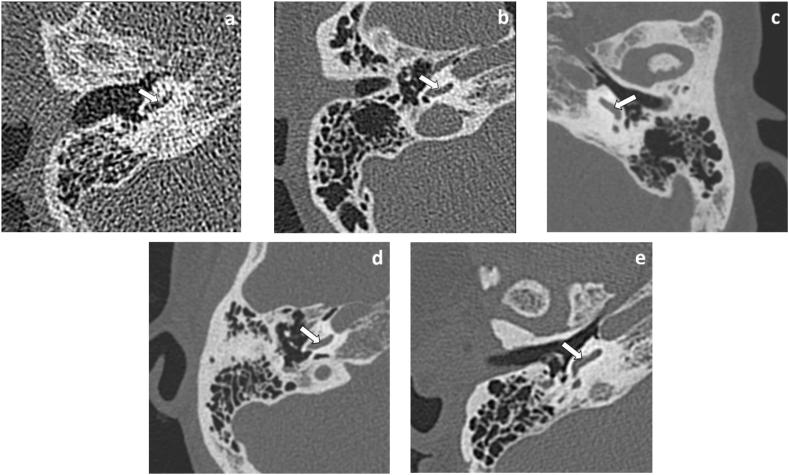

A total of ninety-seven temporal bones from 53 consecutive adult patients who had suspected otitis media and mastoiditis and underwent temporal bone CT were prospectively enrolled. All patients underwent high resolution CT protocol (group A) and an additional low-dose protocol (group B). In group A, high resolution data were reconstructed by filter back projection (FBP). In group B, low-dose data were reconstructed by DLR mild (B1), DLR standard (B2) and DLR strong (B3). The objective image quality was analyzed by measuring the CT value and image noise on the transverse image and calculating the signal-to-noise ratio (SNR) on incudomallear joint, retroauricular muscle, vestibule and subcutaneous fat. Subjective image quality was analyzed by using a five-point scale to evaluate nine anatomical structures of middle and inner ear. The number of temporal bone lesions which involved in five structures of middle ear were assessed in group A, B1, B2 and B3 images.

There were no significant differences in the CT values of the four reconstruction methods at four structures (all p > 0.05). The DLR group B1, B2 and B3 had significantly less image noise and a significantly higher SNR than group A at four structures (all p < 0.001). The group B1 had comparable subjective image quality as group A in nine structures (all p > 0.05), however, the group B3 had lower subjective image quality than group A in modiolus, spiral osseous lamina and stapes (all p < 0.001), the group B2 had lower subjective image quality than group A in modiolus and spiral osseous lamina (both p < 0.05). The number of temporal bone lesions which involved in five structures for group A, B1 and B2 images were no significant difference (all p > 0.05), however, the number of temporal bone lesions which involved in mastoid for group B3 images were significantly more than group A (p < 0.05). The radiation dose of high resolution CT protocol and low-dose protocol were 0.55 mSv and 0.11 mSv, respectively.

Compared with high resolution CT protocol, in the low-dose protocol of temporal bone CT, DLR mild and standard could improve the objective image quality, maintain good subjective image quality and satisfy clinical diagnosis of otitis media and mastoiditis patients.